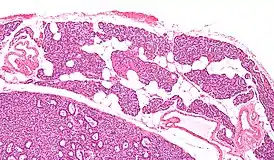

![]() Микропрепарат: Паращитовидная железа — слева внизу аденома паращитовидной железы. |